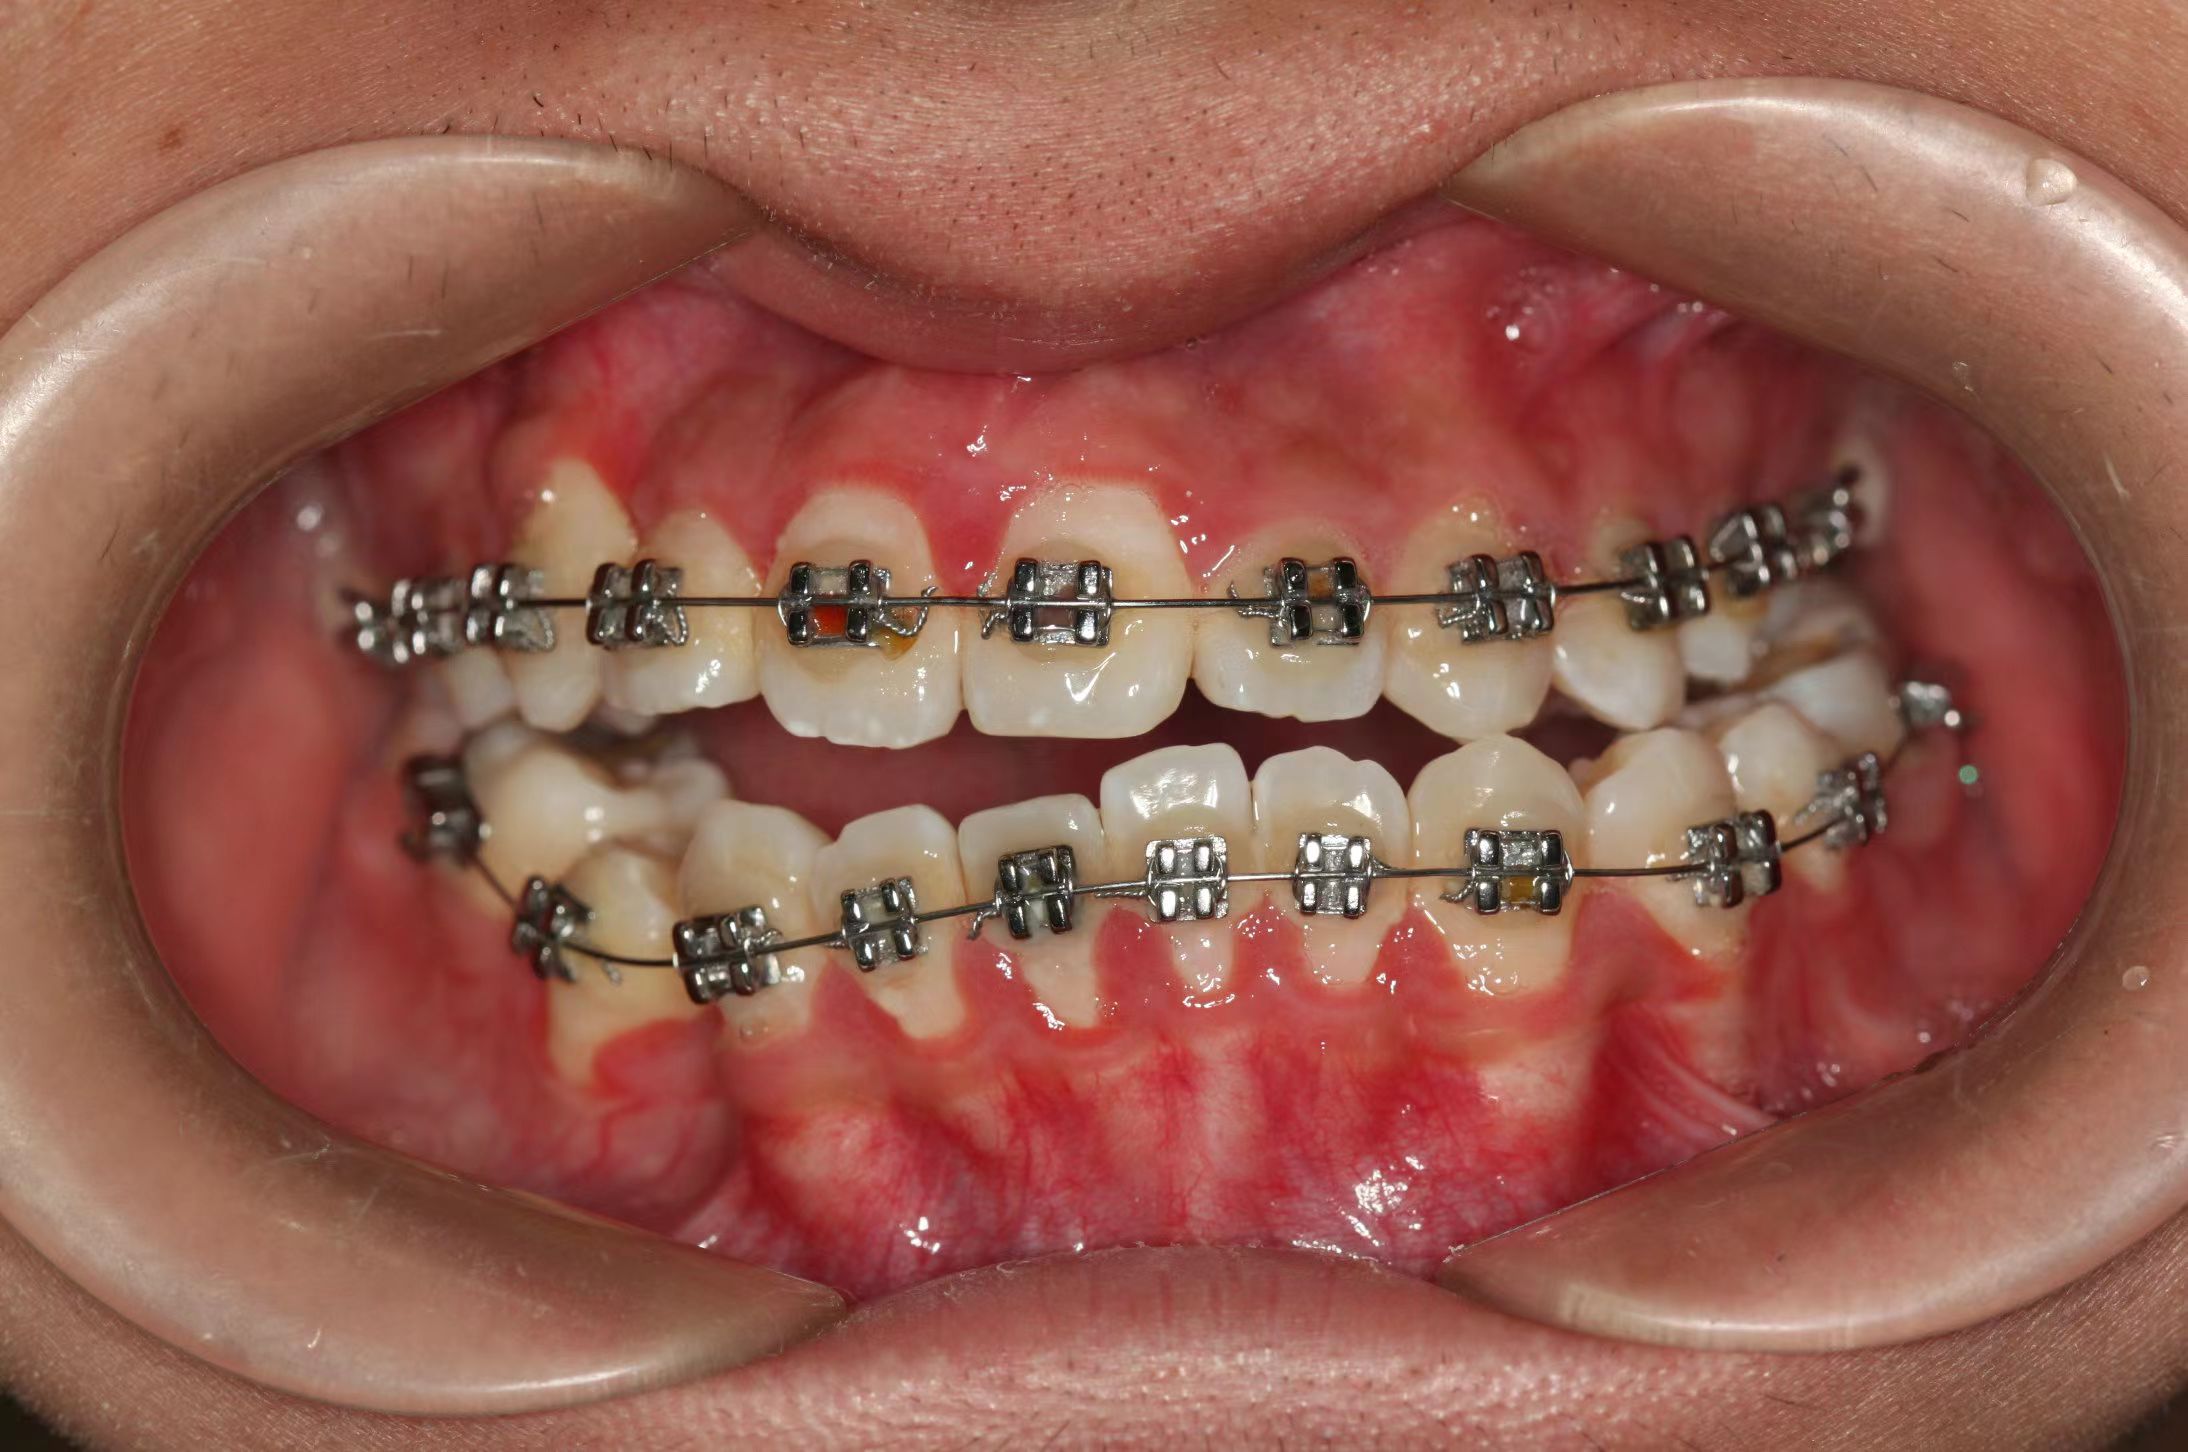

情况:不接受外科手术,在当地做了1年半的矫治,遇到困难无法进行。由外地正畸同行推荐来上海寻求非手术矫治的二手病例。武广增老师接收时的错合畸形情况,呈现严重的骨性反合偏合及侧方开合(图1-图10)。由于推荐其去口腔医院接受正颌外科手术遭到拒绝,武广增老师通过专业的检查、分析,制定一套详细的治疗计划,采用了磨牙推进器技术、武式辅弓技术等特色正畸手段获得明显效果(图2-1~图2-9)。治疗结束后也拍摄了相关照片(图3-1~图3-9)。

矫治前

图1